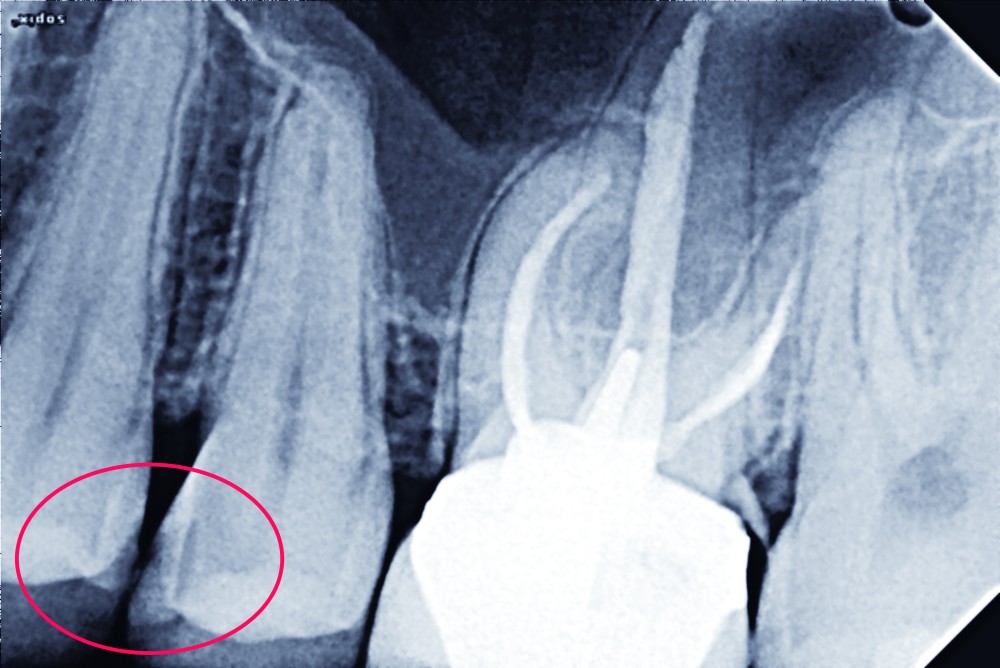

La gestion thérapeutique des lésions carieuses proximales postérieures se heurte à plusieurs complexités tant diagnostiques que techniques. La multiplicité des matériaux commercialisés et la difficulté d’évaluer aussi l’activité carieuse résiduelle compliquent le choix du substitut dentinaire à utiliser, spécialement lors de lésions actives. La transition entre une restauration a minima de type 1, sans aucune préparation ou de type 2, avec préparation tissulaire demeure ténue. Les bases des traitements proposés dans ce report de cas dérivent du concept LIFEDT ou light induced fluorescence for diagnosis and treatment. Cet exposé se propose de traiter deux lésions carieuses proximales (Site 2) contiguës, l’une de stade 3 et l’autre de stade 1.